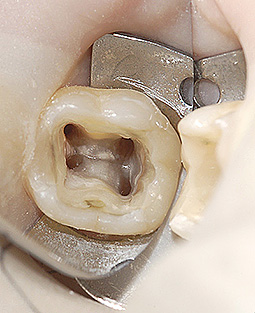

La prima fase della terapia è la corretta esecuzione di una radiografia diagnostica/preoperatoria al fine di ottenere tutte le informazioni sull’anatomia del dente in esame, successivamente si deve isolare il dente con la diga di gomma; è questo un presidio indispensabile per l’esecuzione di una corretta terapia il cui obiettivo è quello di disinfettare e detergere un sistema canalare (endodonto), e dunque il primo passo da fare è quello di evitare di contaminarlo ulteriormente con i batteri di cui la saliva è ricca. Il dente isolato con la diga di gomma è infatti completamente separato dal resto della bocca, garantendo un’ottimale detersione chimica da un lato e preservando il paziente dalla involontaria ingestione di disinfettanti o strumentario.

Dopo aver isolato il dente si inizia a rimuovere l’otturazione o la corona del dente da trattare e si esegue una corretta apertura della camera pulpare, al fine di ottenere un accesso diretto al sistema dei canali radicolari.